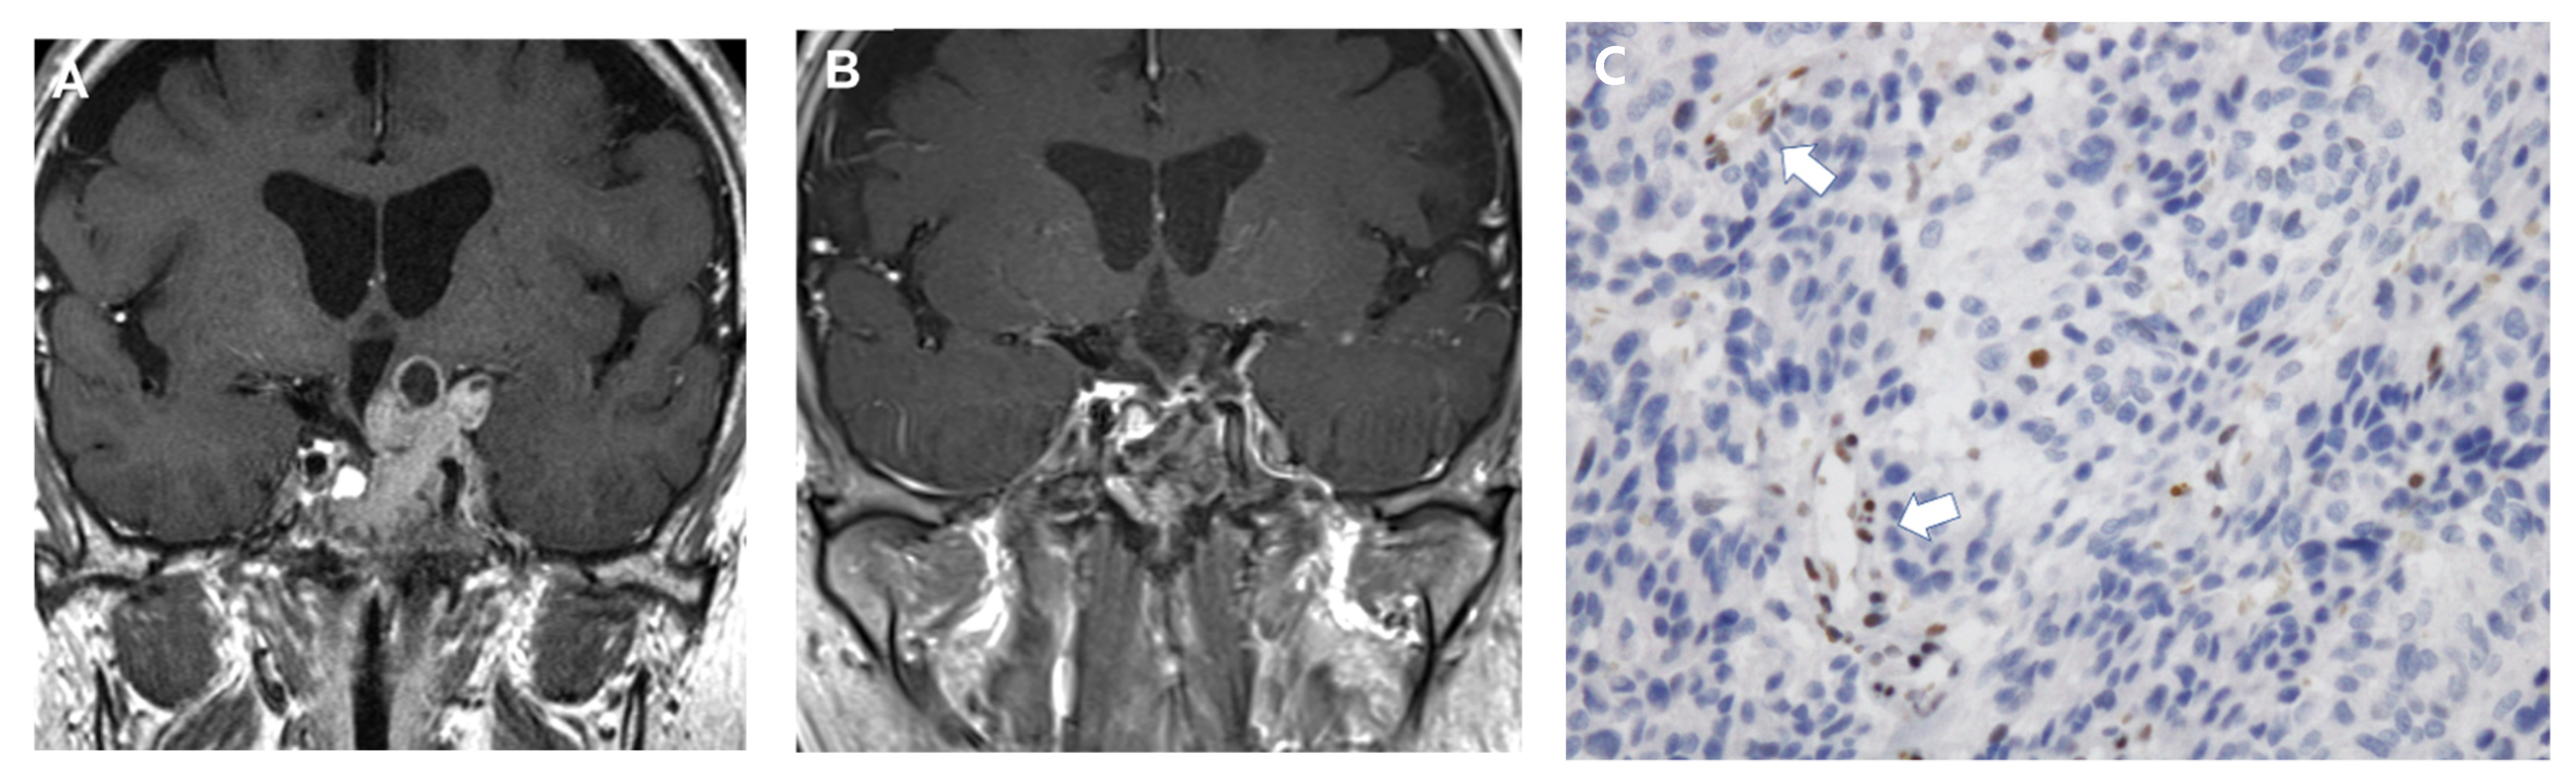

- Amano, E.; Nishiyama, M.; Iwasaki, Y.; Matsushima, S.; Oguri, H.; Fukuhara, N.; Nishioka, H.; Yamada, S.; Inoshita, N.; Fukaya, T.; et al. Remarkable cystic expansion of microprolactinoma causing diabetes insipidus during pregnancy. J. Clin. Endocrinol. Metab. 2012, 97, 2575–2576. [Google Scholar] [CrossRef] [PubMed]